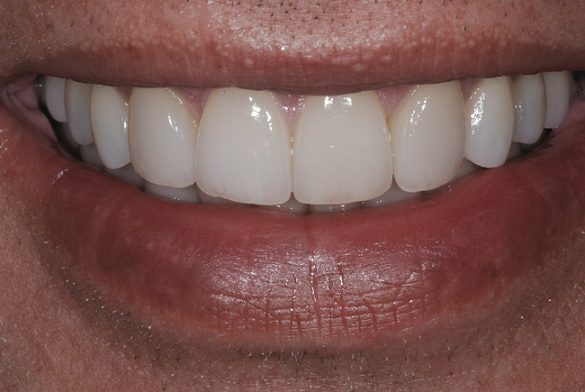

Fotografiile finale ale acestui caz au pus în evidenţă genul de rezultate care se pot obţine urmând sistemele şi tehnicile dovedite (fig. 8-11). S-au realizat obiectivele de îmbunătăţire a raportului “alb-roz” alături de cele legate de zâmbetul pacientului. Perceperea în mod clar a obiectivelor acestui caz şi capacitatea de a comunica cu acurateţe cu pacientul şi ceramistul reprezintă o parte din cheia succesului.

Utilizarea camerelor digitale şi a tehnologiei de amprentare digitală permite durate de livrare mai scurte şi eficientizate, cu îmbunătăţirea abilităţii de comunicare. Acest caz este un exemplu al modului în care planificarea şi comunicarea adecvată produce rezultate sporite, rezultate clinice excelente şi o estetică funcţională îmbunătăţită.20 La momentul publicării, pacientul se afla la şedinţa de evaluare după un an, fără nicio problemă raportată sau diagnosticată.